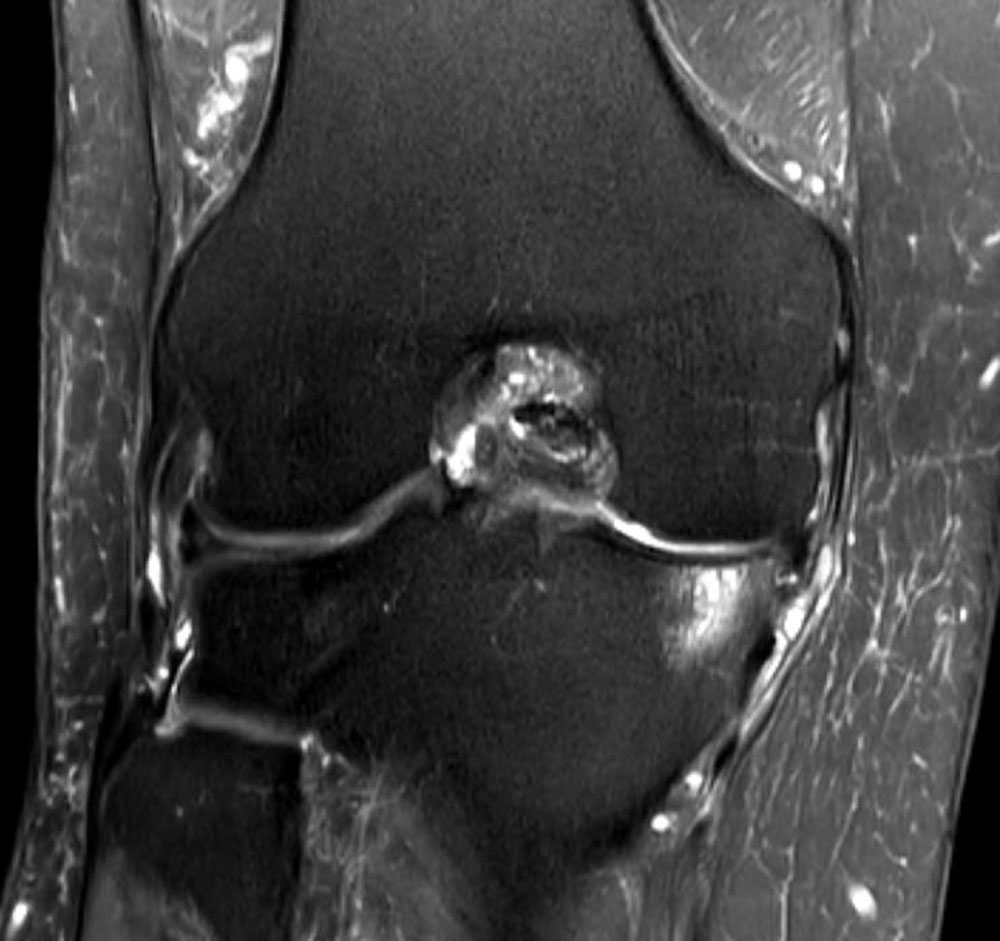

- MRT Knie Coronar T2

Die Kernspintomographie wird vor allem herangezogen, wenn es darum geht, komplexe Weichteil-und Knochenveränderungen nachzuweisen. Auch entzündliche Vorgänge oder Verletzungen mit Flüssigkeitsansammlungen in den Gelenken können damit aufgedeckt werden.

Die kernspintomographische Untersuchung basiert auf einem starken Magnetfeld, das in der engen Untersuchungsröhre vorliegt. Die Untersuchung dauert meist über 30 Minuten und wird aufgrund der lauten Geräusche durch die Spulen als unangenehm empfunden. Gerade zum Nachweis von Bandscheibenveränderung ist die Kernspintomographie das Mittel der Wahl.